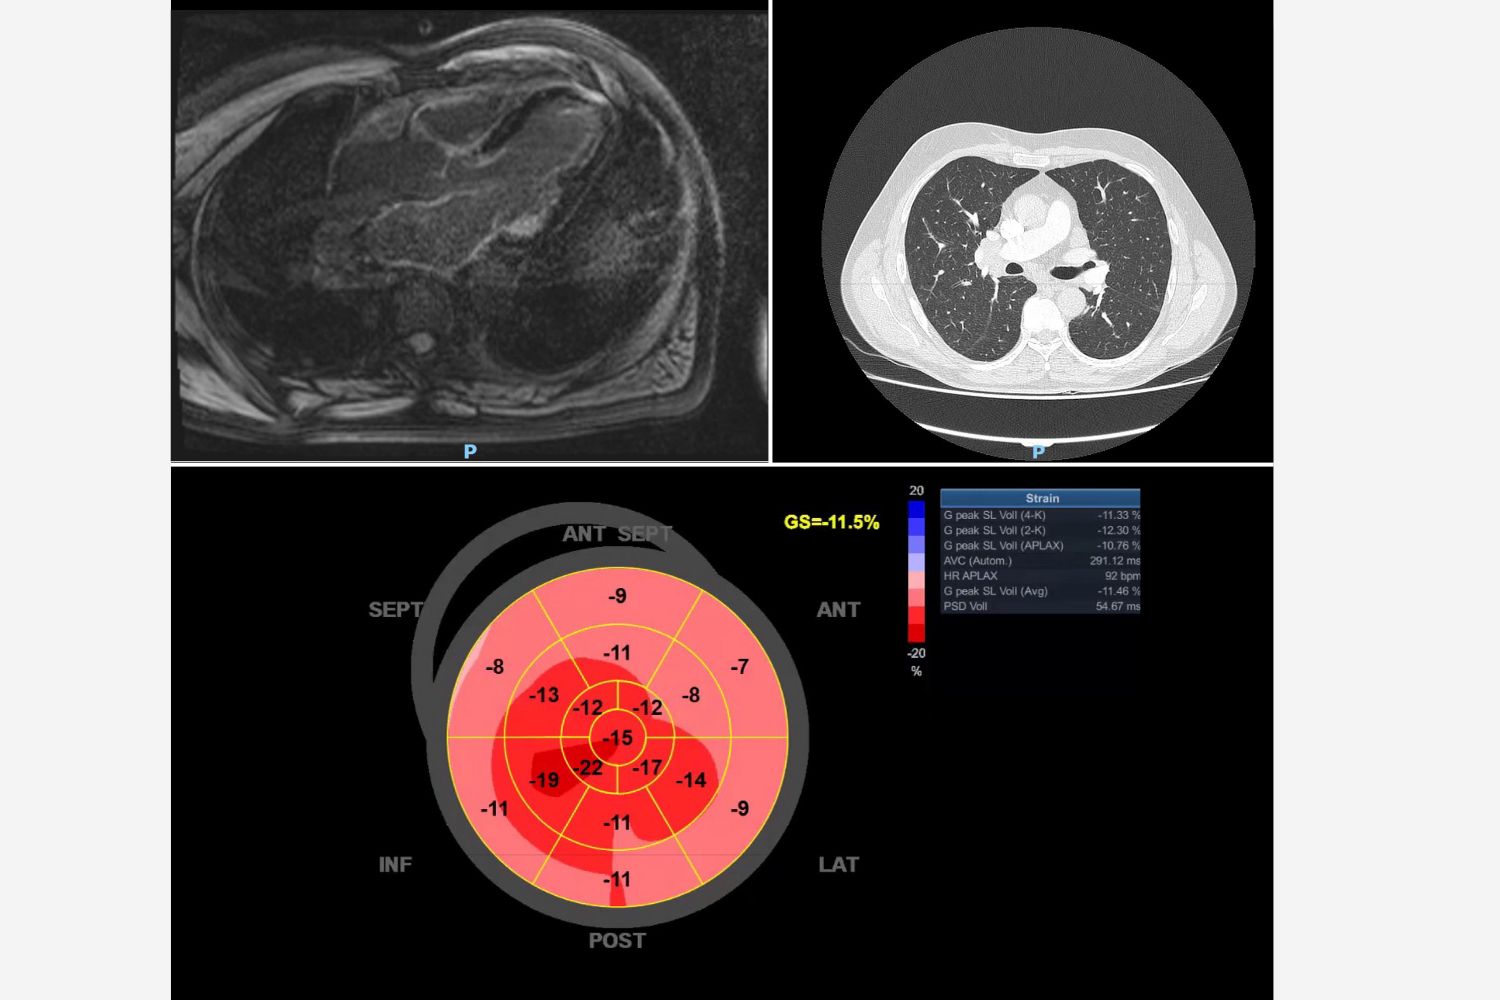

Image of the Week - 8 May 2024

Doctor Vijay Soorampally

Doctor Bharath Raj Kidambi

Doctor Sriram Veeraraghavan